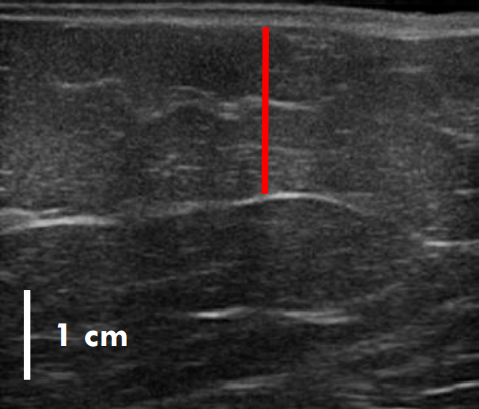

실제 지방이 어느 정도 감소했는지는 초음파 사진을 보면 더욱 뚜렷하게 확인할 수 있는데.

트루스컬프ID 시술 전, 12주 후

초음파를 비교한 사진입니다.

레드 라인이 지방층의 두께입니다.

앞서 보여드린 사례의 경우 시술 전과 비교했을 때 약 36% 정도 지방이 감소한 결과를 볼 수 있는데요.